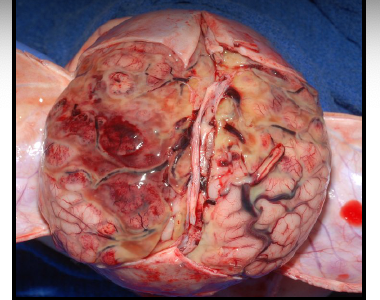

maceration

degenerative changes in fetal tissue when retained in utero